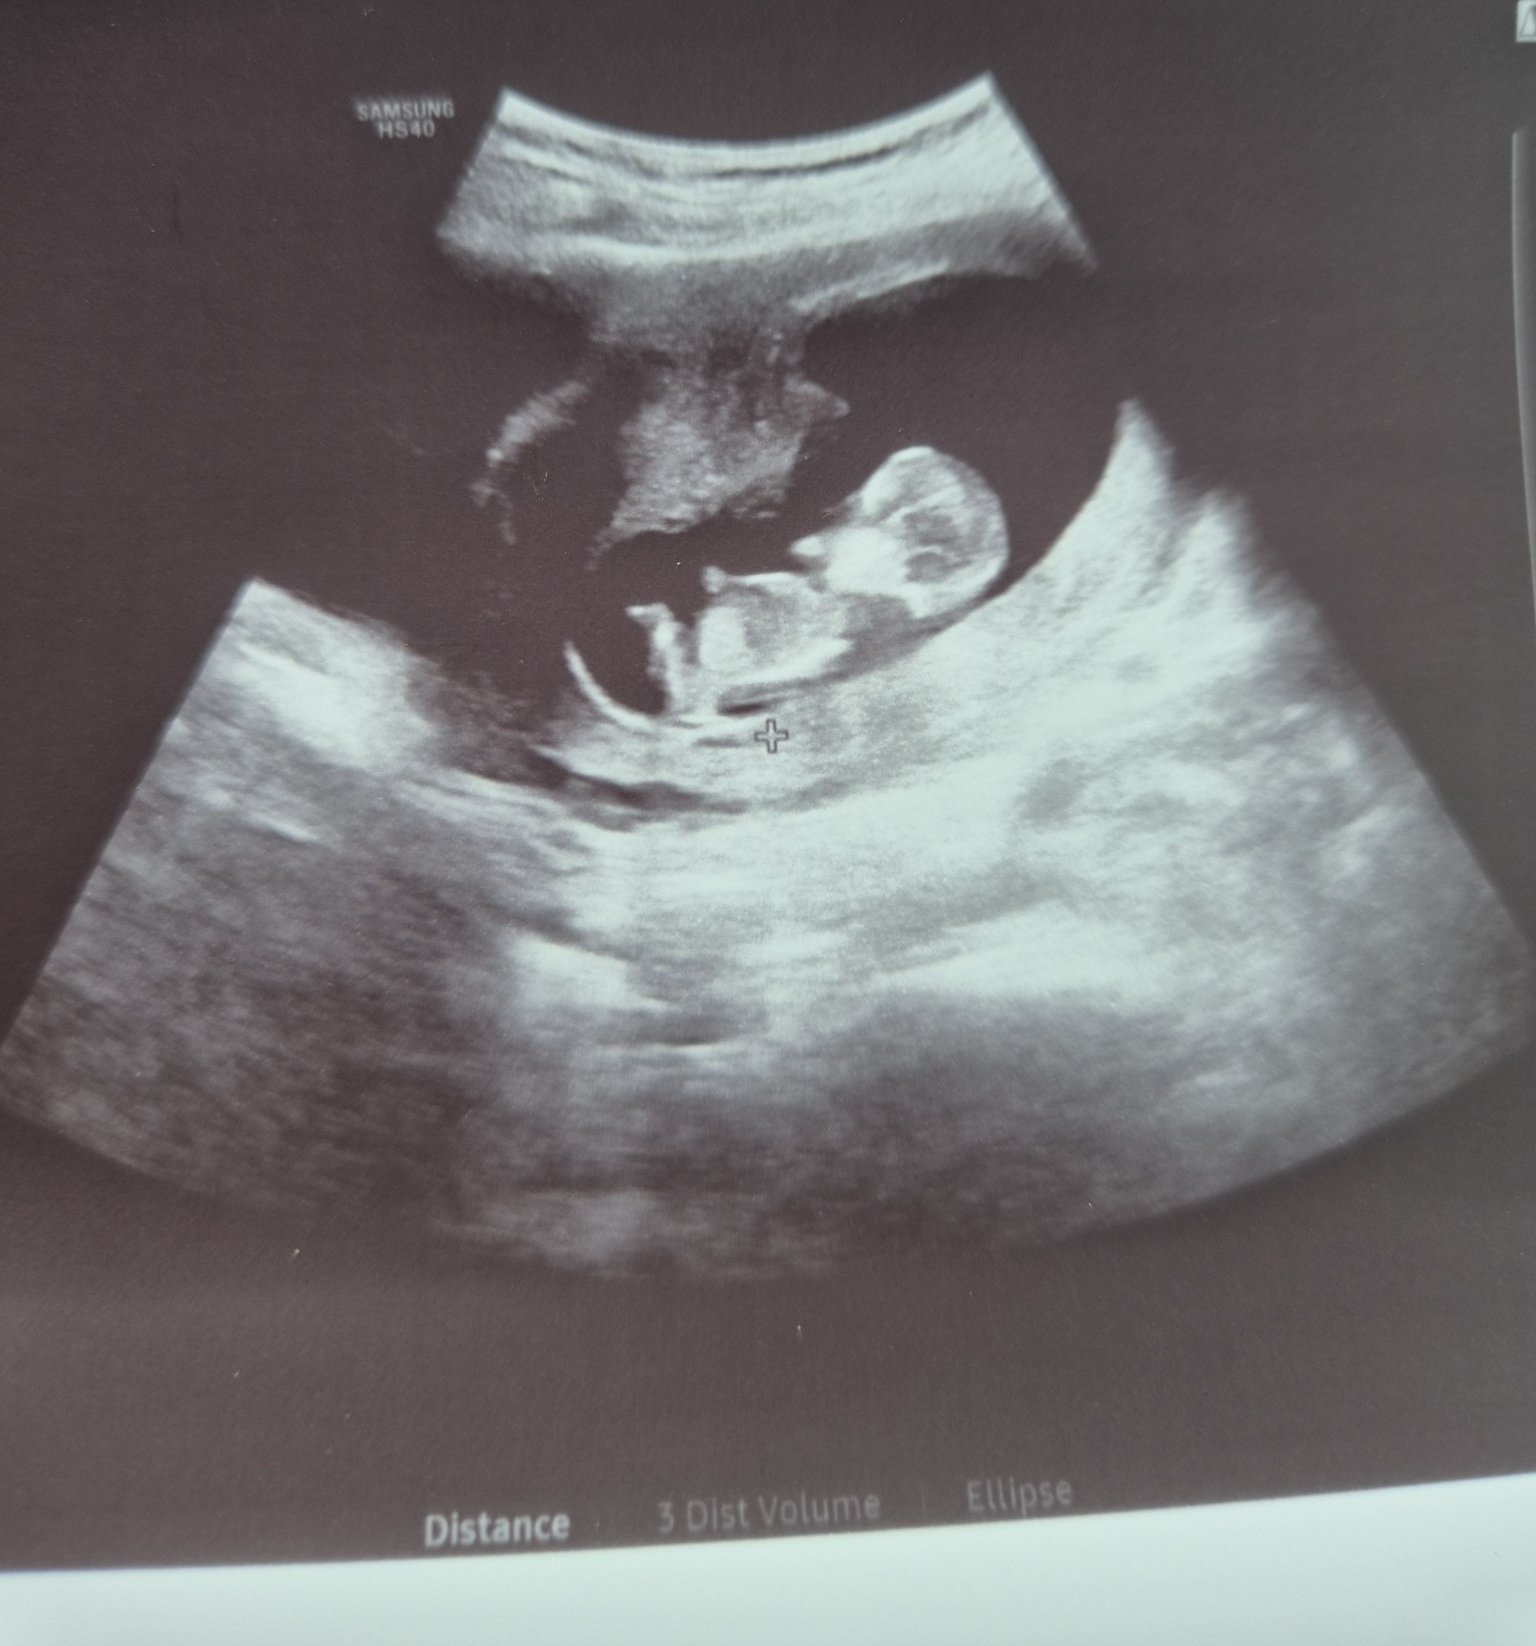

Здравейте, някой дали може да разпознае пола на бебето ..?

Предполагам и залагам на МОМЧЕ !!! 89%давам , че не греша 😂

Ако лекарят не е успял да види не знам как се очаква ние да познаем. Можем да хвърлим един боб.

За тази цел си има УЗ и лекари. Ако твоя лекар не може да го определи, защо ние да можем? Снимката в коя г.с. е правена??? Пол се определя след 12 г,с, а може и още по-късно. Ако искаш да знаеш със сигурност пусни се пренатален тест.